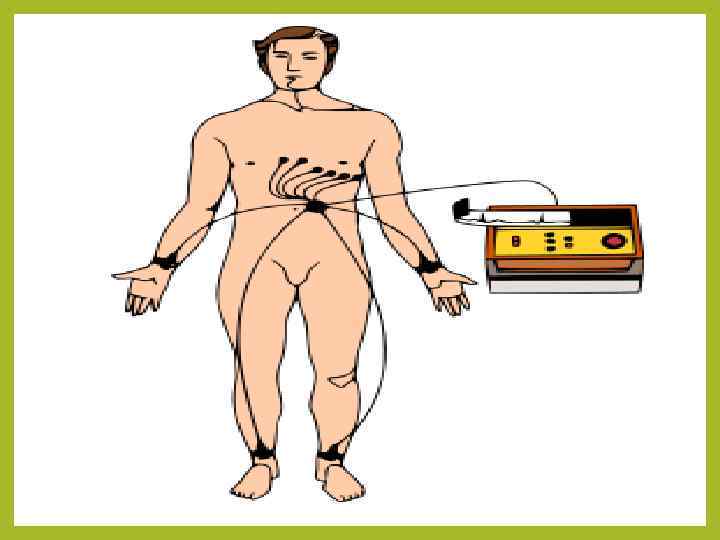

ЭКГ